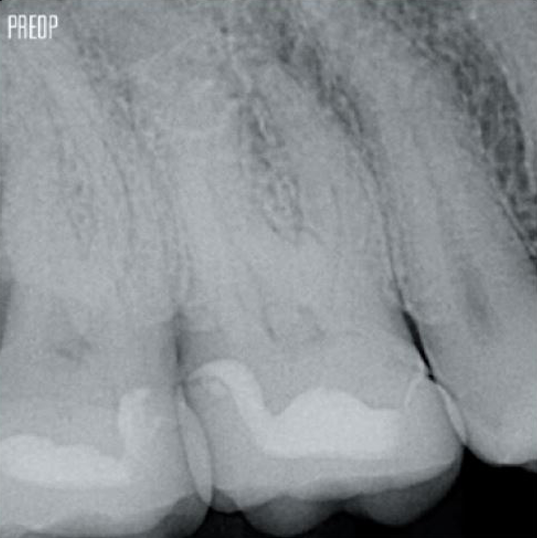

Fotos cortesía del Dr. Ahmed Salman

Un tratamiento exitoso de conducto radicular comienza con un acceso adecuado a la cámara pulpar. El procedimiento ideal proporciona acceso a la entrada del conducto radicular con una pérdida mínima de dentina.

Se recomienda utilizar una cavidad endodóntica conservadora (Conservative Endodontic Cavity, CEC) con el sistema TruNatomy®.

Más conservación de dentina. Se garantiza la conformación, irrigación y obturación adecuadas.